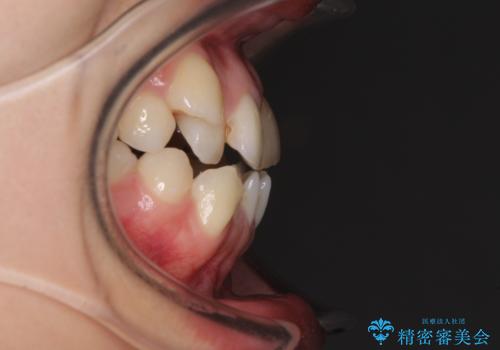

- 上の八重歯を気にして来院された患者様です。

受け口傾向にあるため、上顎前歯の叢生解消とともに下顎前歯を後方へ移動させることを目的とし、上下左右の第一小臼歯4歯を抜歯することとしました。

受け口傾向の方の下顎抜歯矯正では、下顎前歯の歯肉が退縮することがあります。前歯を移動させるときには、歯肉退縮が起こらないように工夫する必要があります。